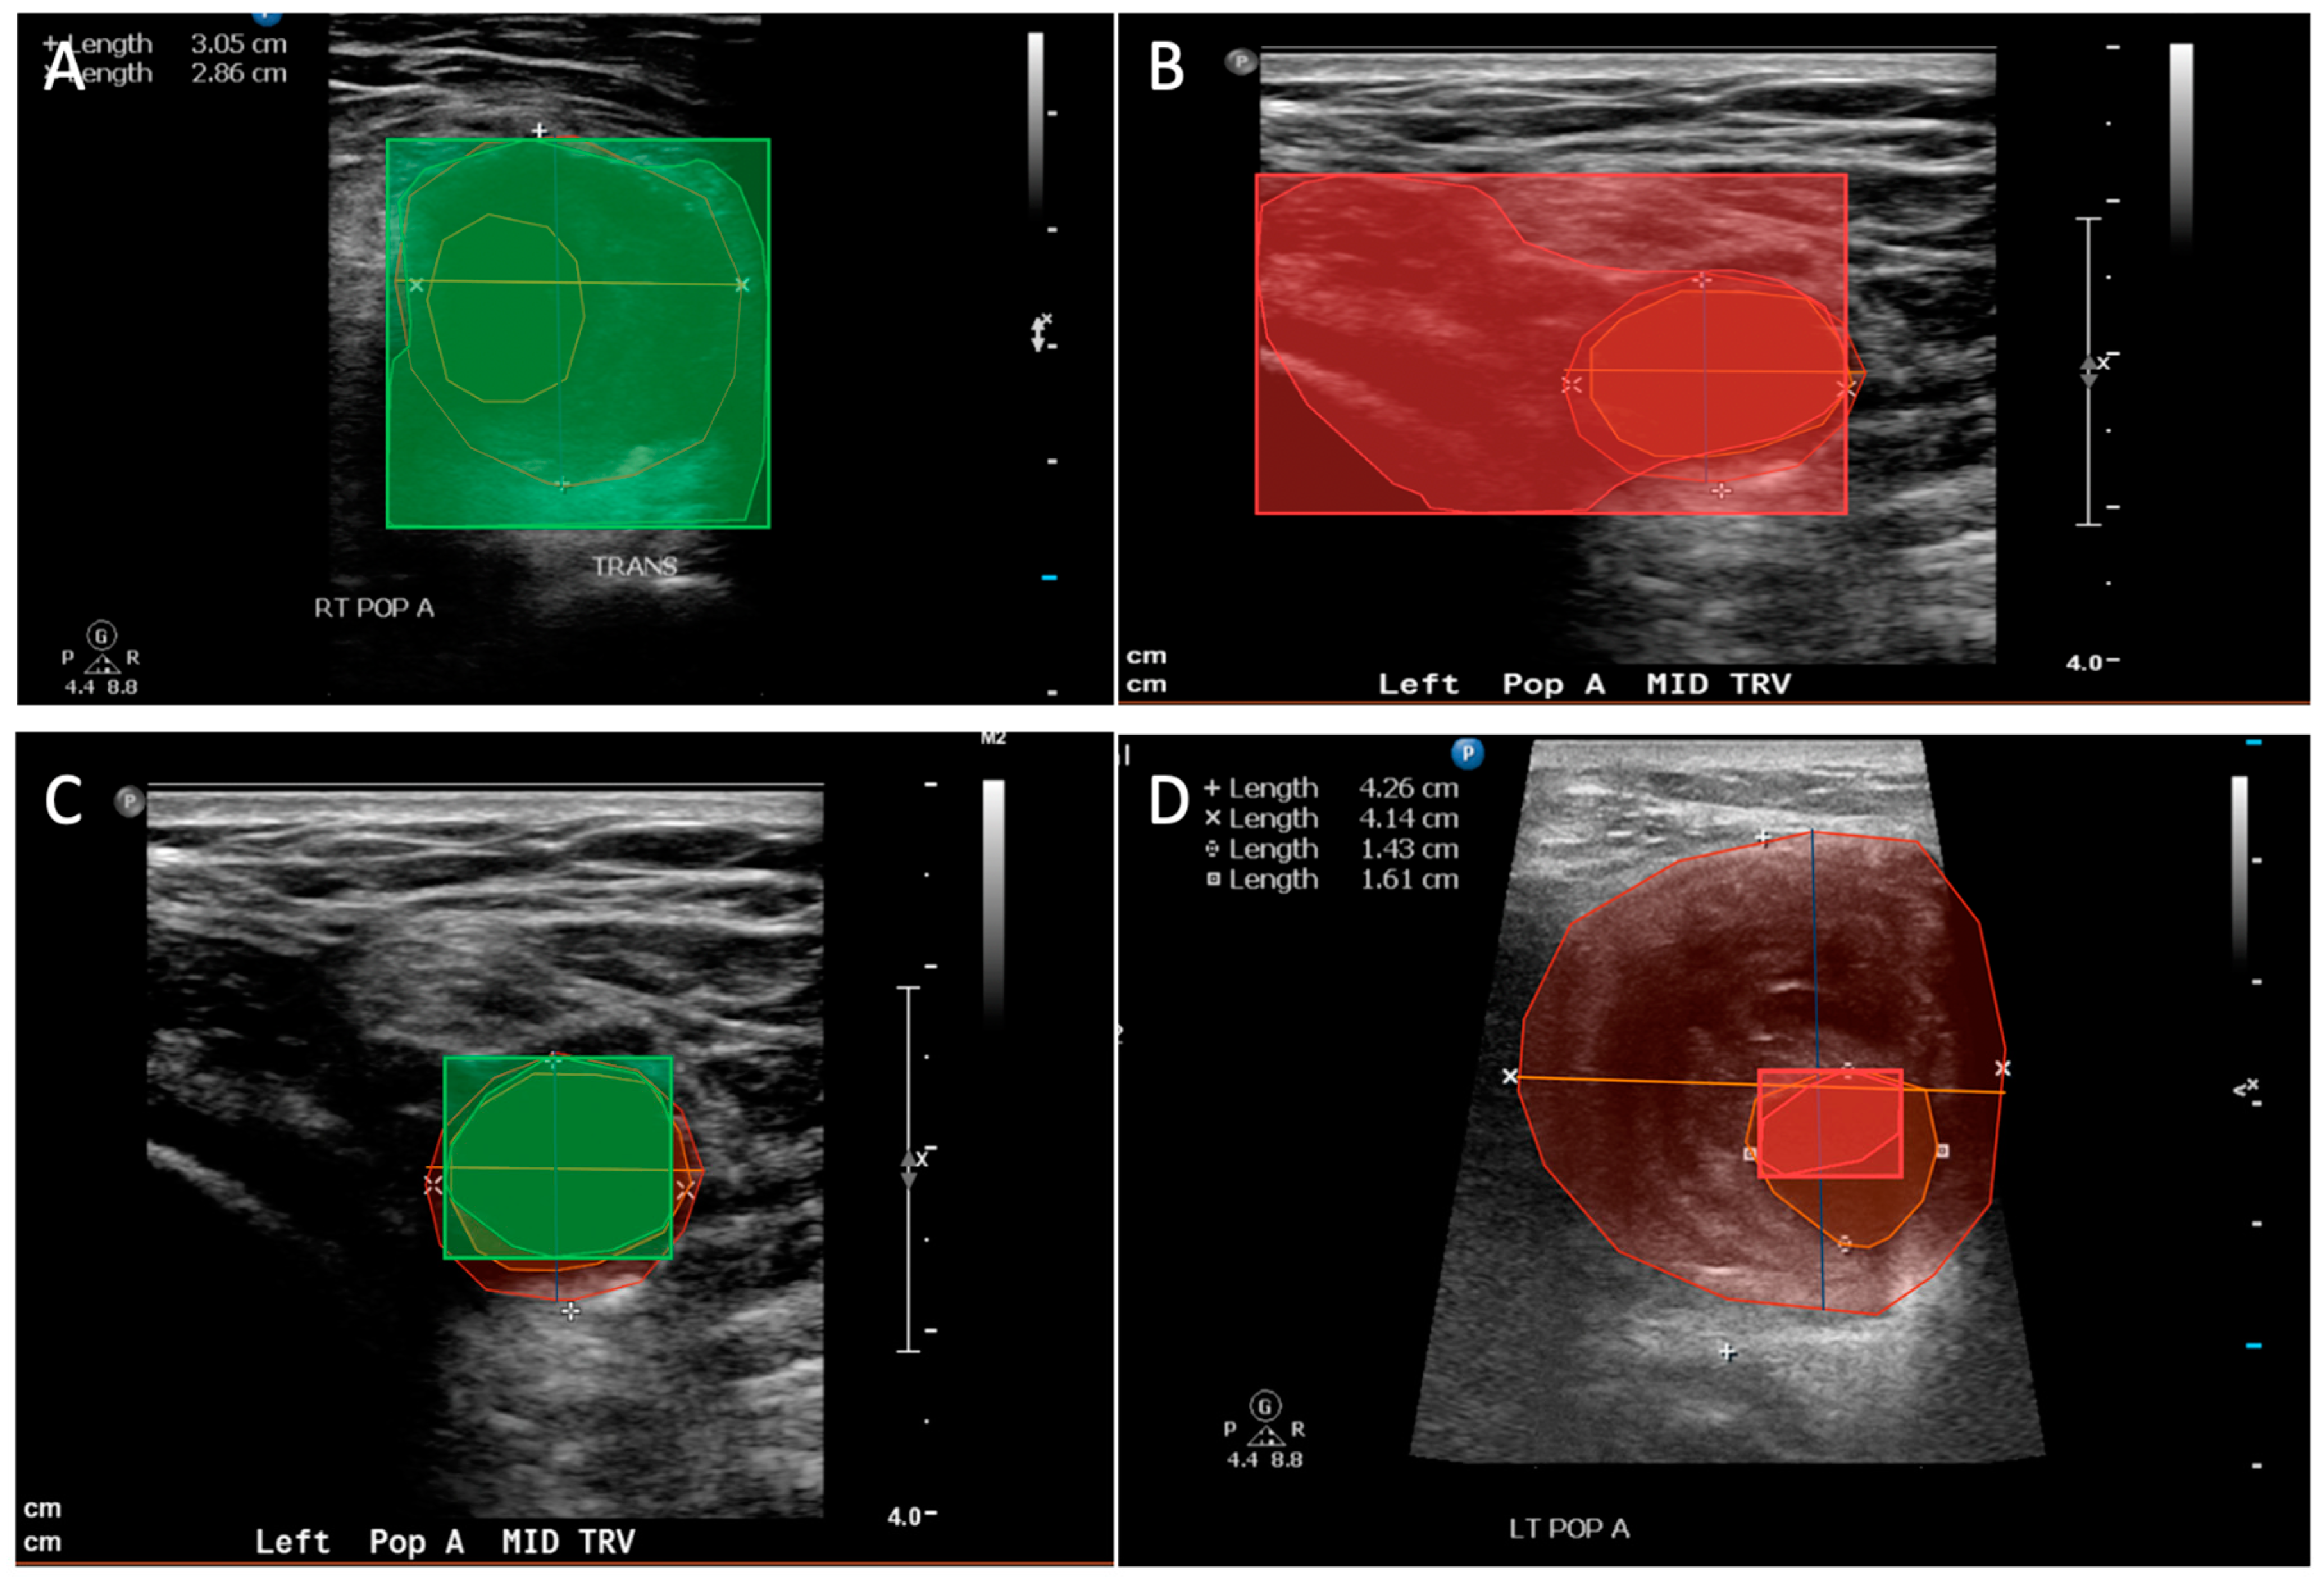

- Bellomo, T.; Goudot Guillaume Gaston Brandon Lella, S.; Jessula, S.; Sumetsky, N.; Beardsley, J.; Patel, S.; Fischetti, C.; Zacharias, N.; Dua, A. Popliteal artery aneurysm ultrasound criteria for reporting characteristics. J. Vasc. Med. 2023. [Google Scholar] [CrossRef] [PubMed]

- Bellomo, T.R.; Goudot, G.; Lella, S.K.; Gaston, B.; Sumetsky, N.; Bs, S.P.; Brunson Bs, A.; Beardsley Bs, J.; Zacharias, N.; Dua, A. Percent Thrombus Outperforms Size in Predicting Popliteal Artery Aneurysm Related Thromboembolic Events. medRxiv 2023, 2023, 283–289. [Google Scholar] [CrossRef]